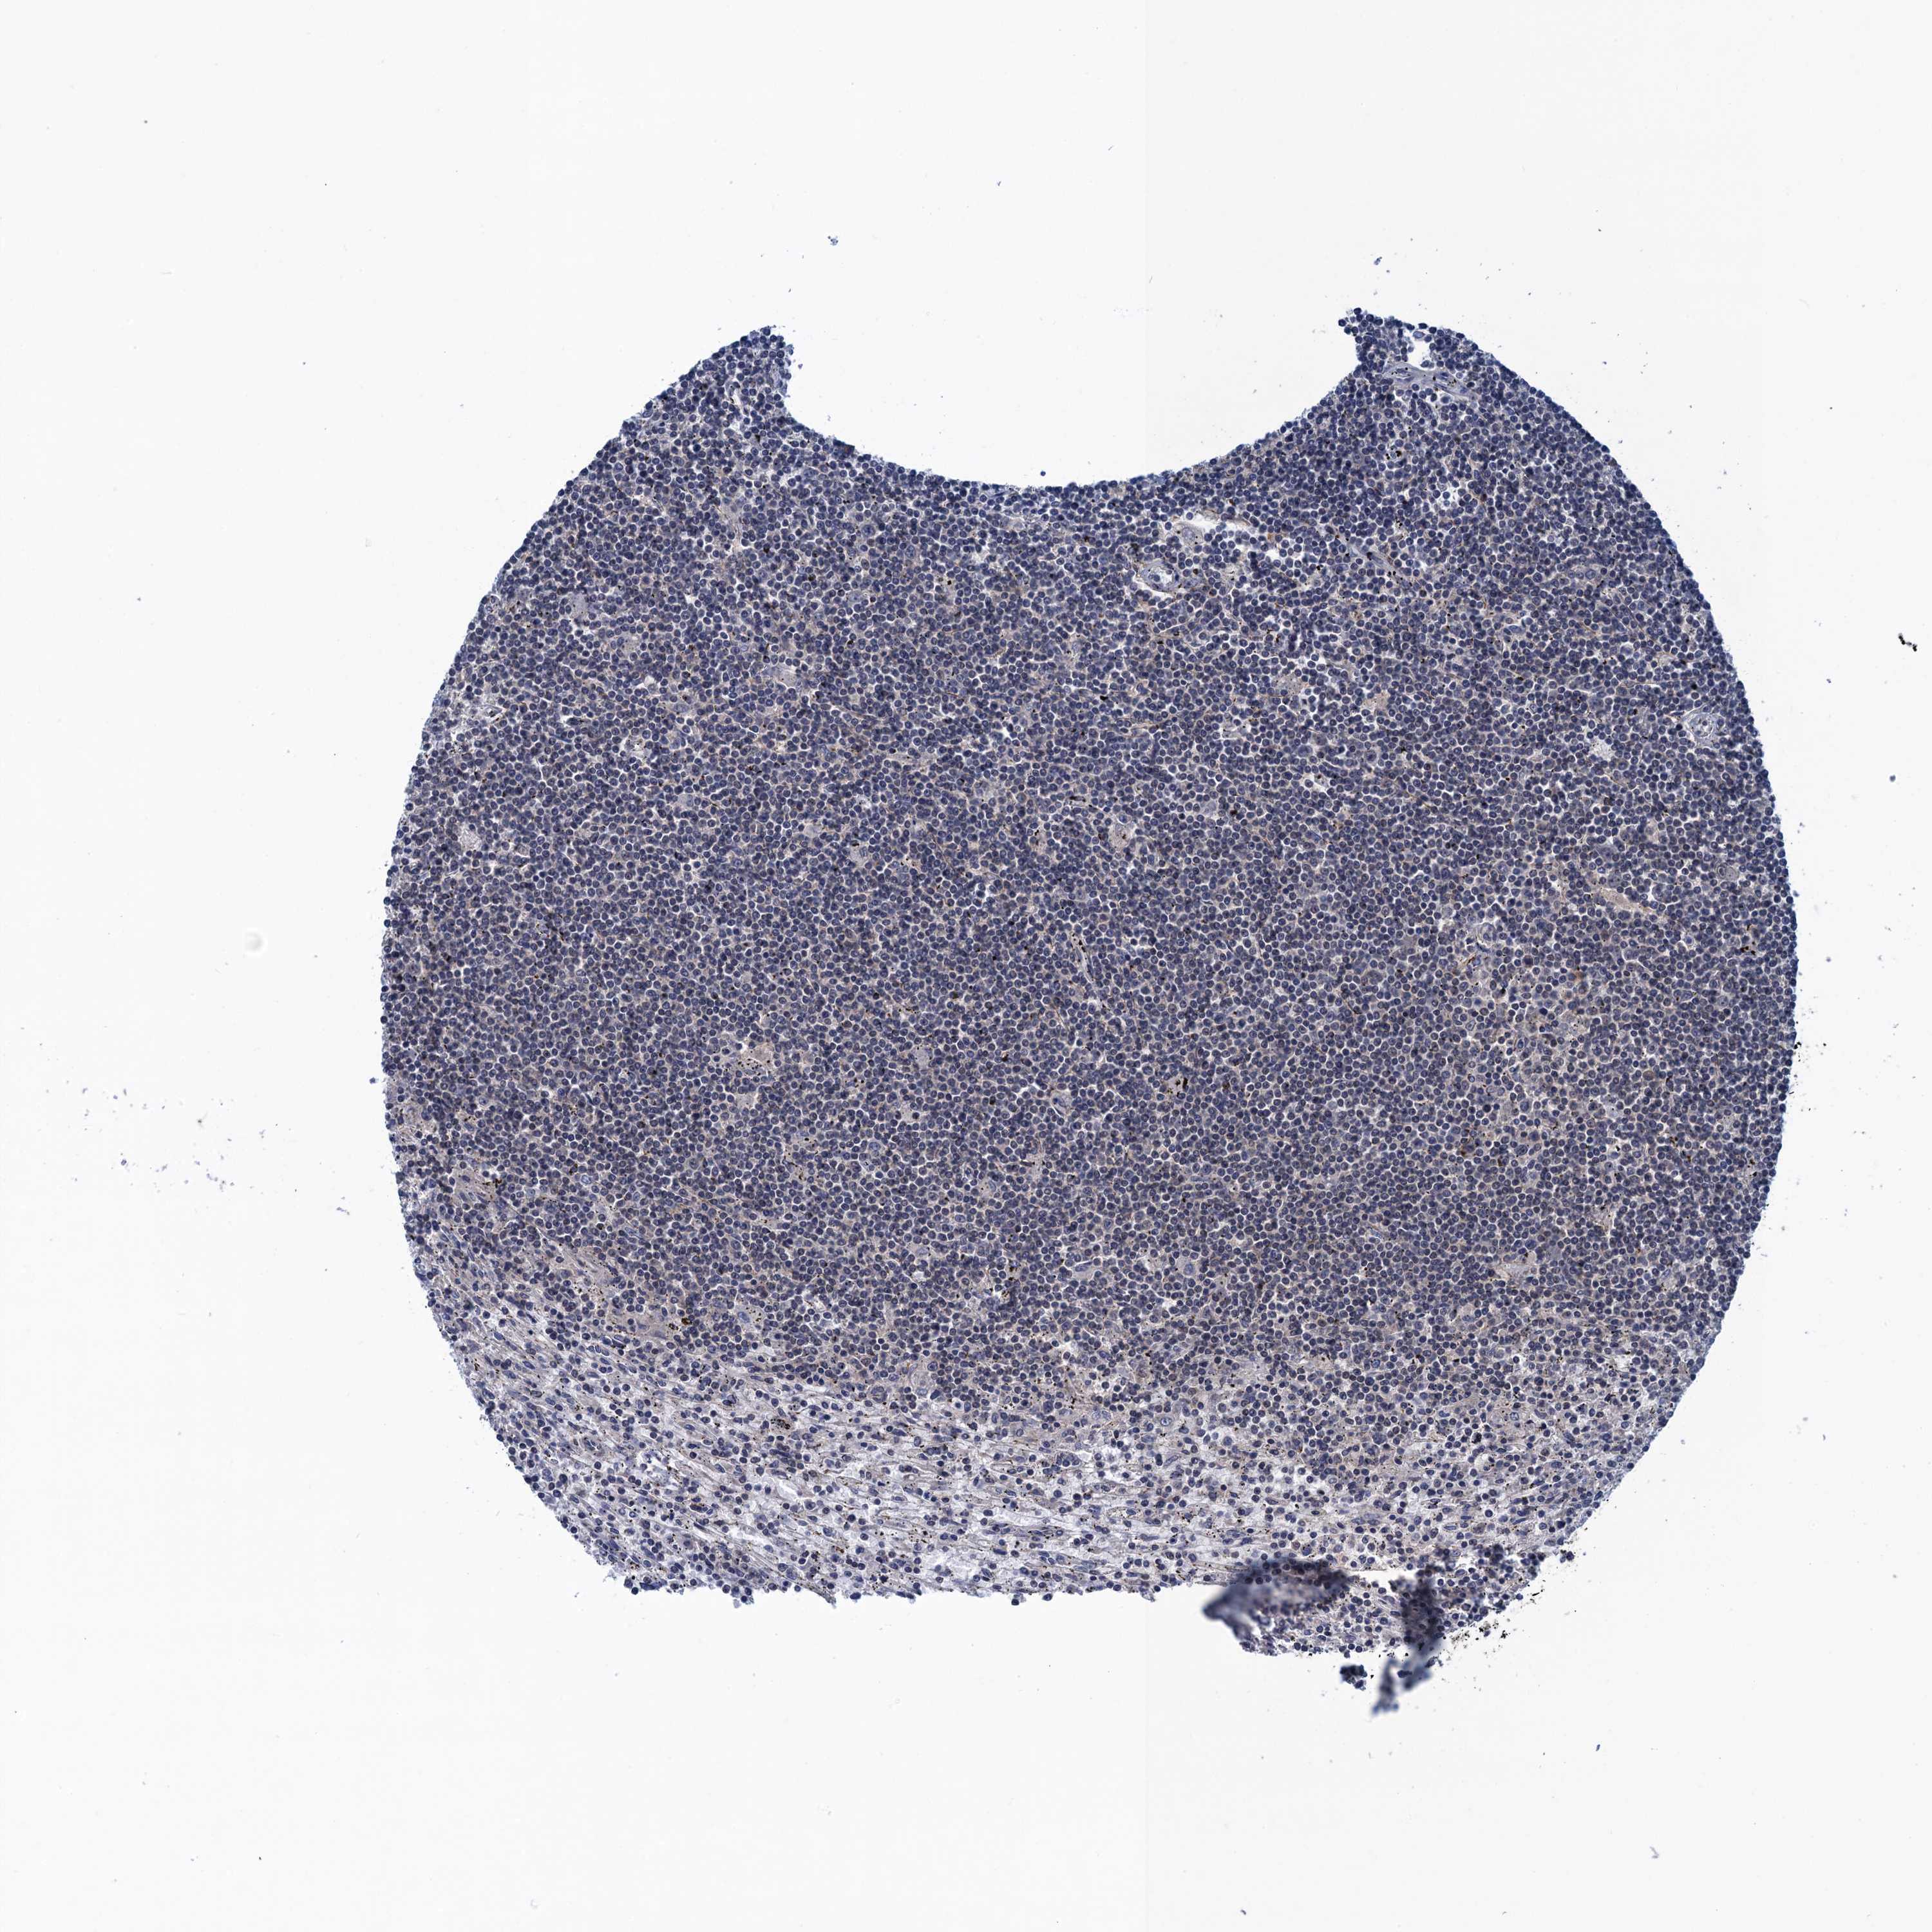

CANCER LYMPHOMA Show tissue menu

LYMPHOMA - Protein expressioni

A mouse-over function shows sample information and annotation data. Click on an image to view it in a full screen mode. Samples can be filtered based on level of antibody staining by selecting one or several of the following categories: high, medium, low and not detected. The assay and annotation is described here.

Each image is clickable and will lead to virtual microscopy that enables deeper exploration of all samples and also displays staining intensity scores, fraction scores and subcellular localization as well as patient and tissue information for each sample.

Antibody HPA041906

Antibody HPA043552

Staining

High

Medium

Low

Not detected

Intensity

Strong

Moderate

Weak

Negative

Quantity

>75%

75%-25%

<25%

None

Location

Nuclear

Cytoplasmic/membranous

Cytoplasmic/membranous,nuclear

Hodgkin's disease, NOS

Malignant lymphoma, non-Hodgkin's type, High grade

Malignant lymphoma, non-Hodgkin's type, Low grade